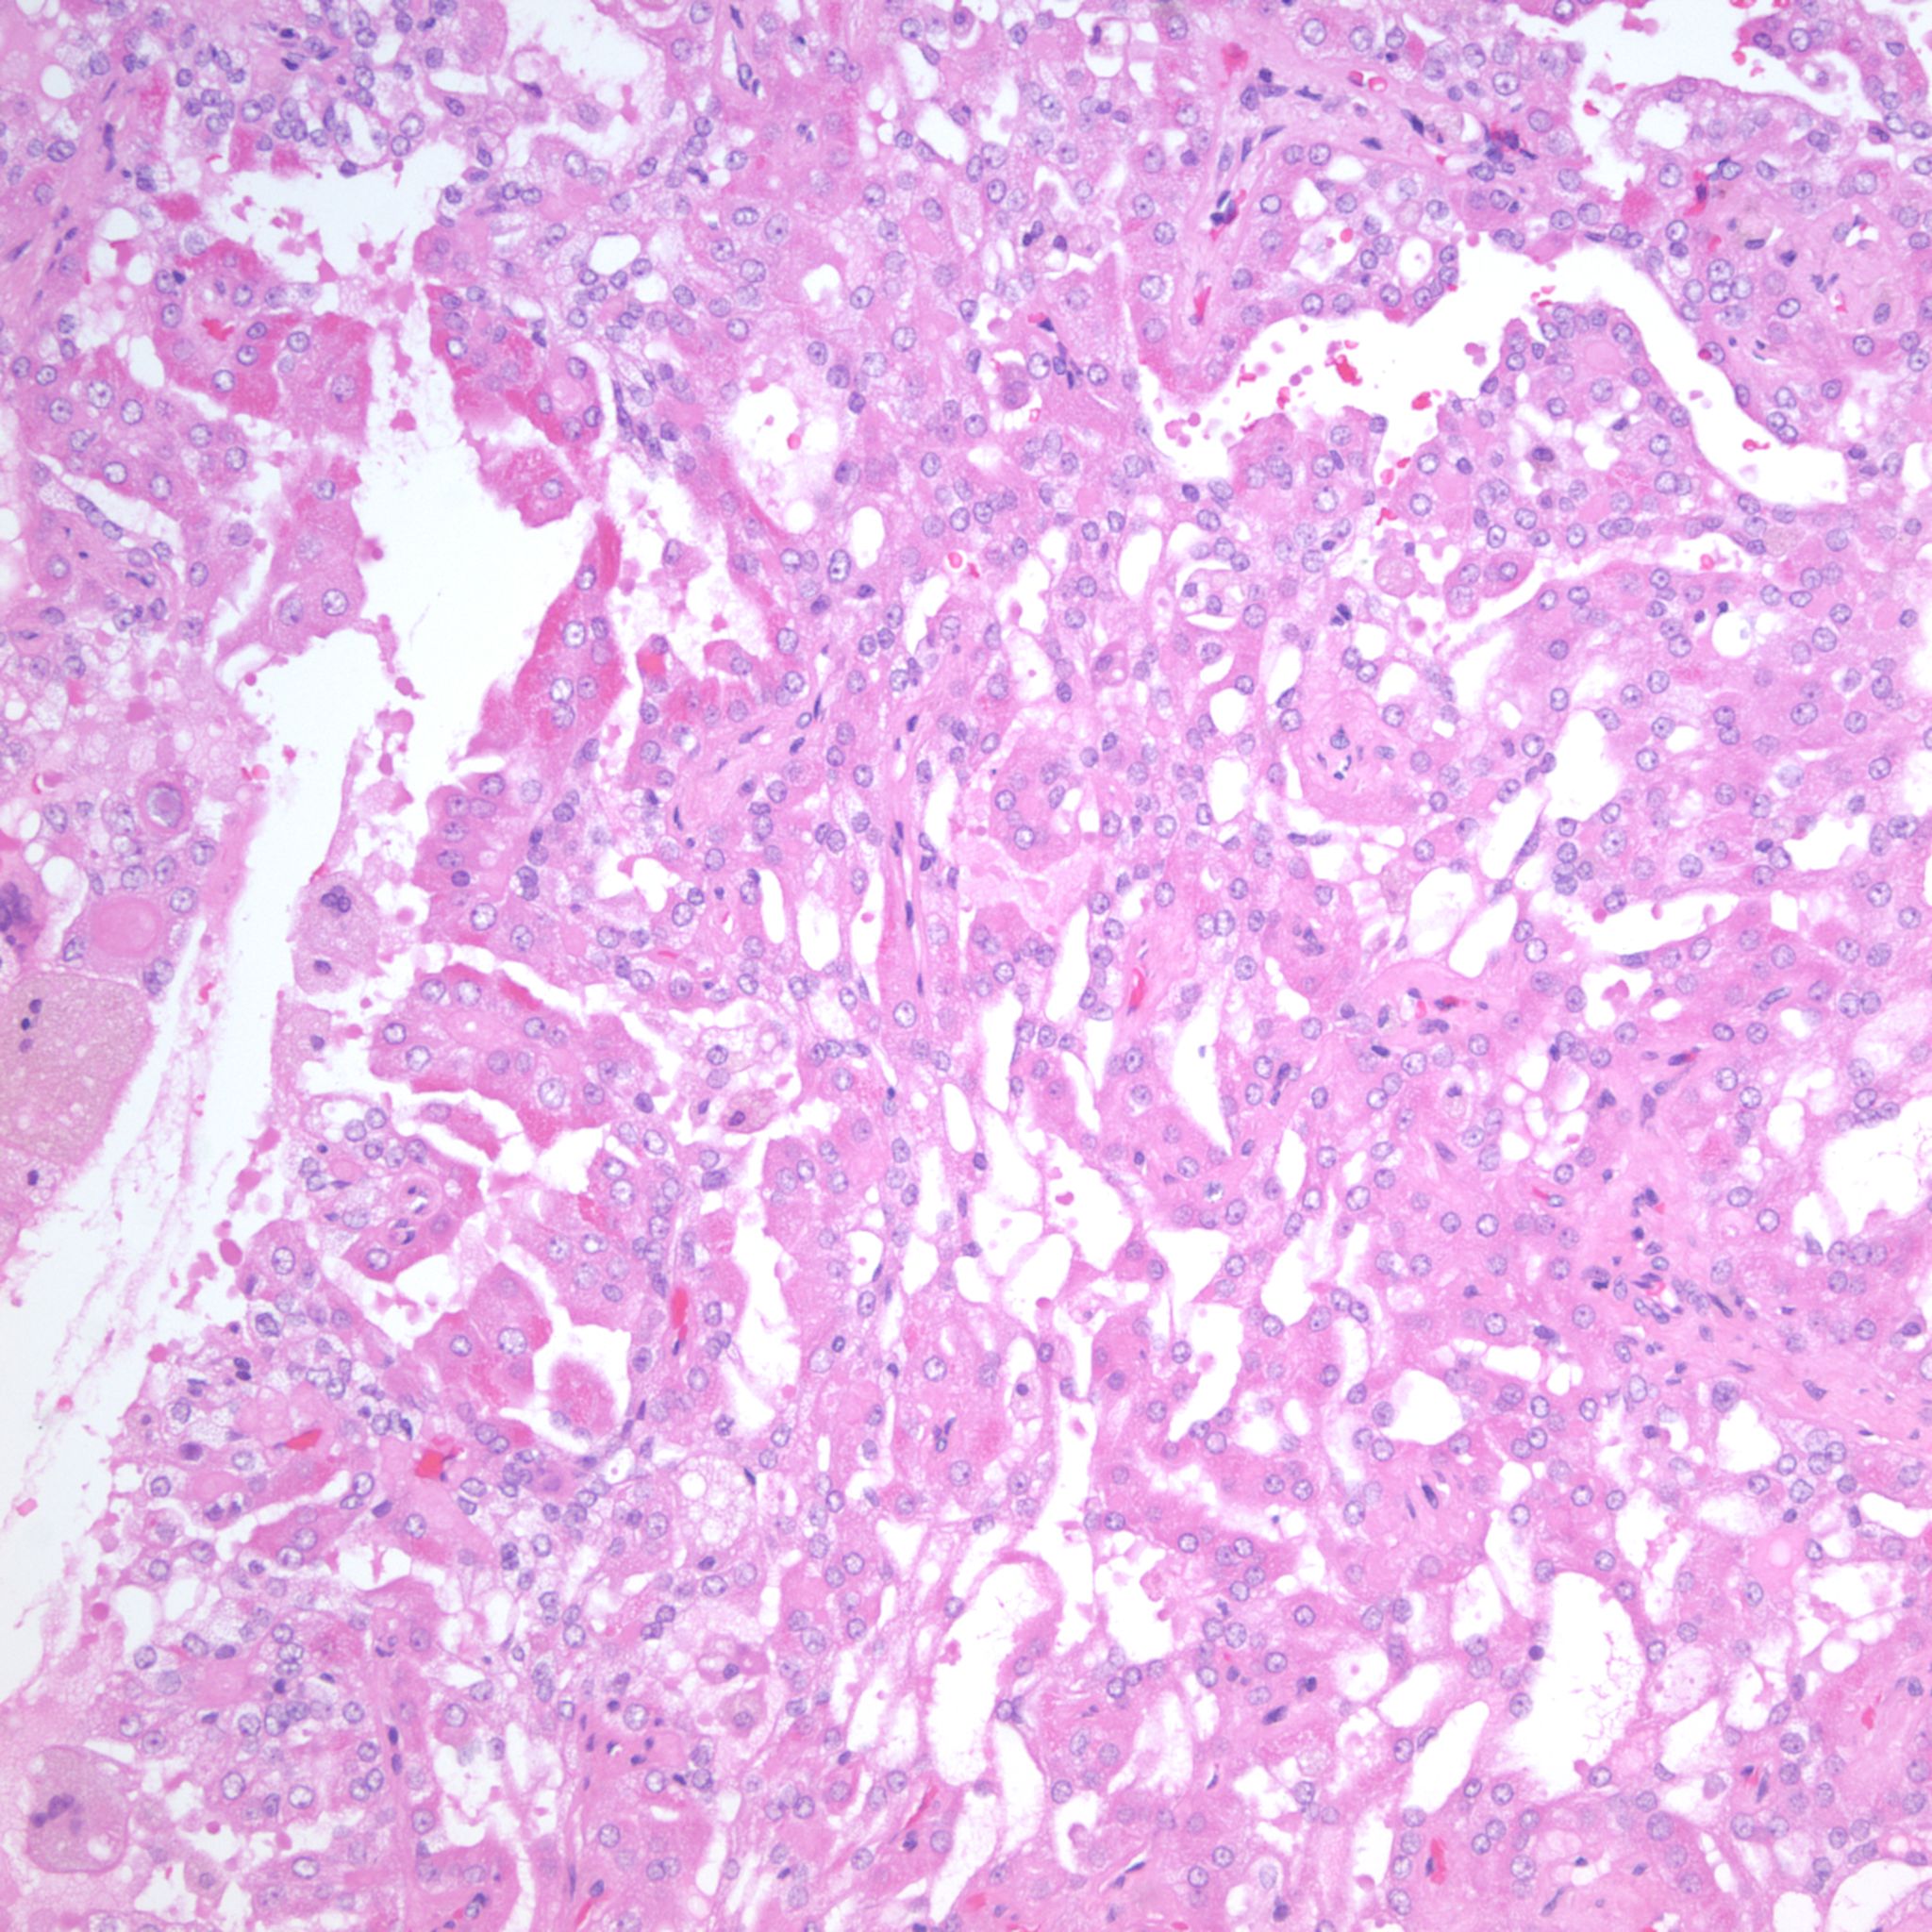

Classification of renal tumors

Case ID: 1237